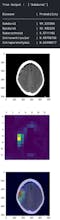

An AI powered webapp that automatically diagnoses various diseases from XRays and CT Scans.It generates prediction heatmaps which makes the AI's predictions more interpretable.Users get automatic confirmation in the prediction from verified radiologists in-app